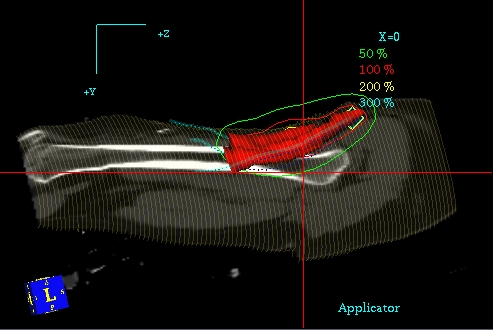

Planowanie 3D PLATO - przekrój podłużny, widoczny CTV, rozkład izodoz